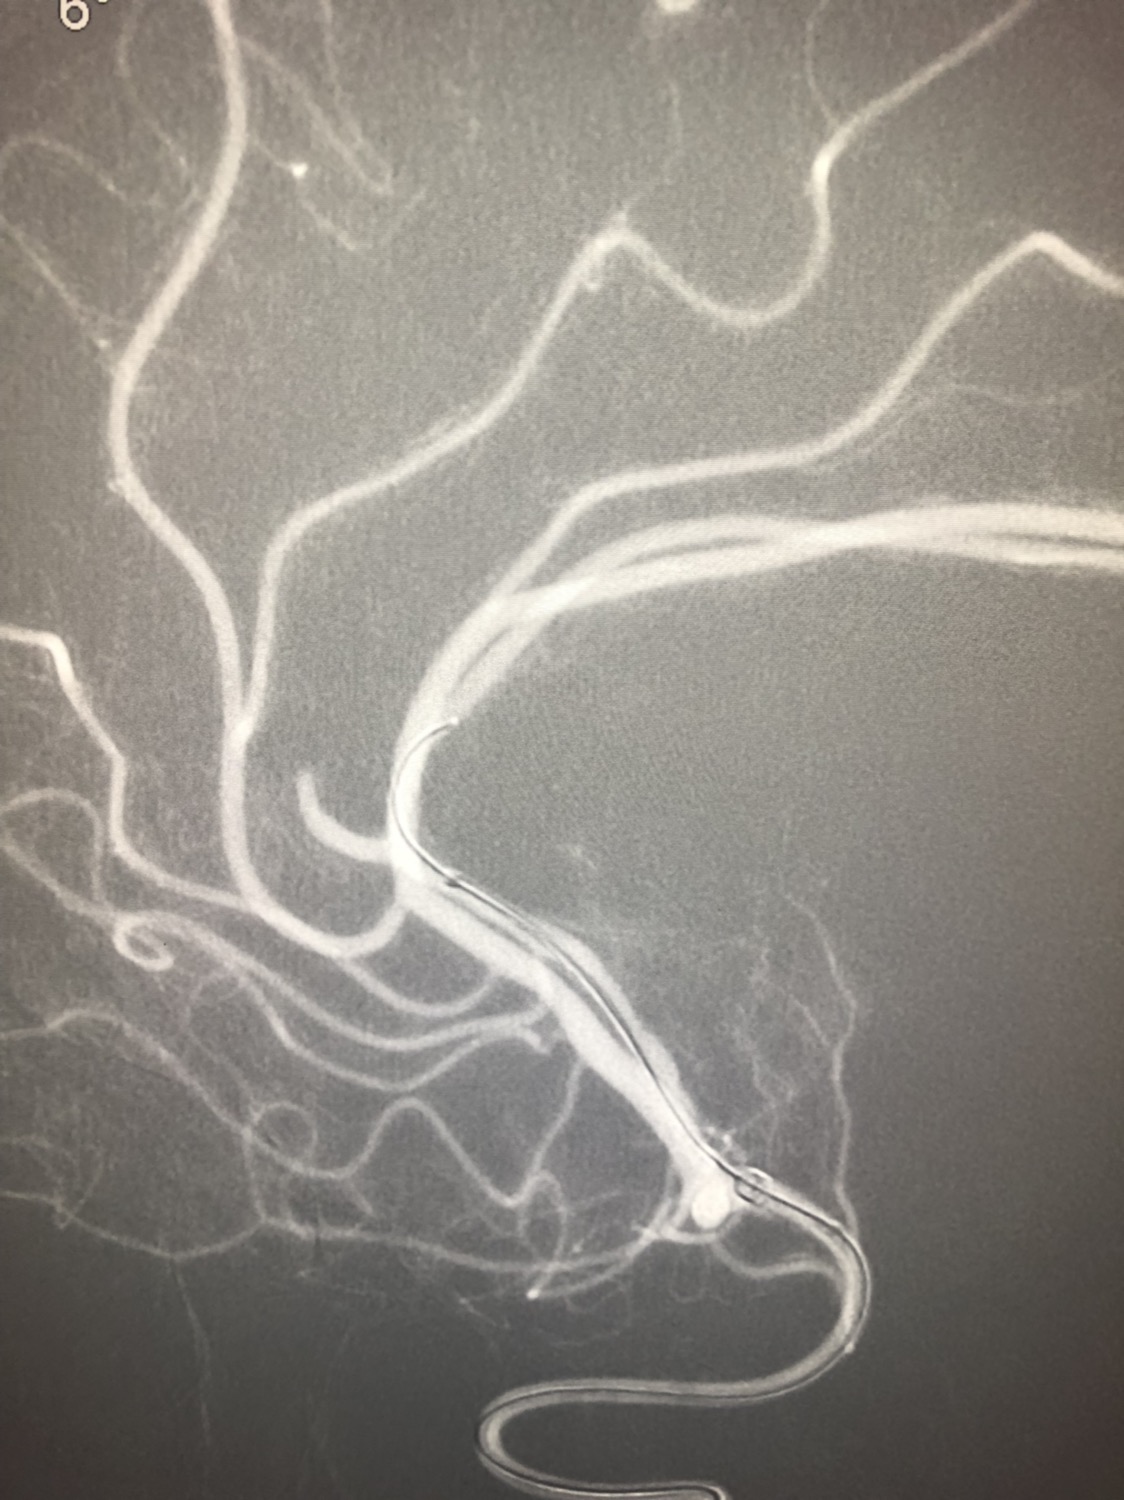

1周前房颤栓塞肱动脉,切开取栓后服用利伐沙班3天。突发偏瘫凝视3小时。上台看M3、A3血栓,国产普威森6f125cm抽吸导管高到位结合尼科3x20mm小支架,结合精细操作,m3和a3的血栓也可以轻松取出。不刺激血管。加造影射线16min两次取栓两个血管再通。

柔软的国产普威森微导管,高到位。

3x20mm的国产reco支架,适合分支血管取栓。

术后良好。